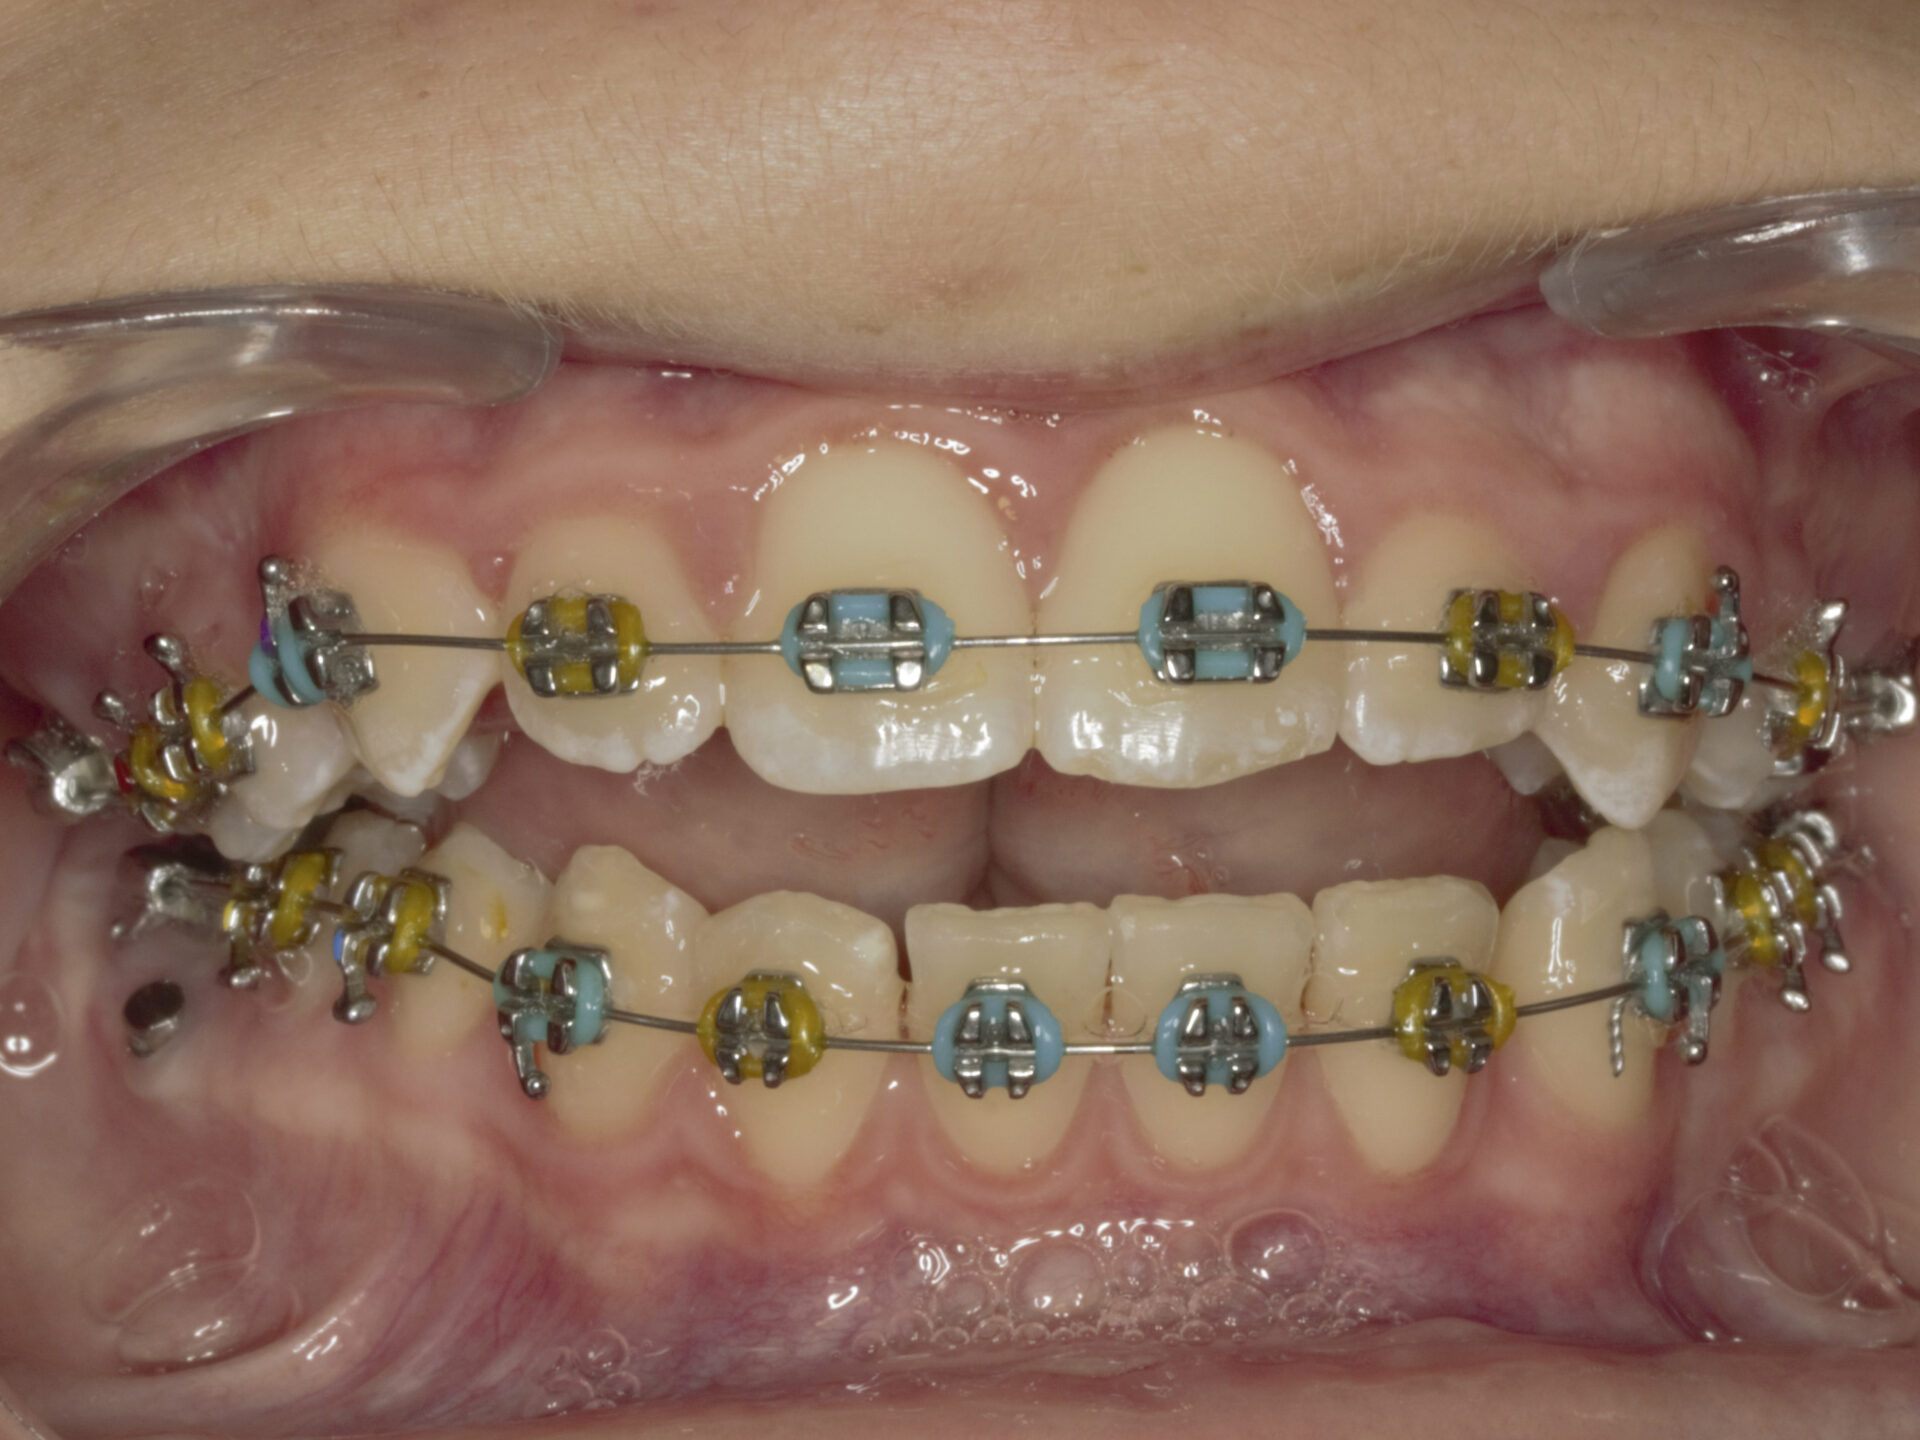

En el análisis intraoral, encontramos una Clase II molar con una mordida tijera completa del lado derecho con una pérdida de la dimensión vertical y una oclusión de los molares superiores contra la encía de la arcada inferior. Además, la paciente presenta una sobremordida de >2/3 y la imposibilidad de erupción de pieza 13, 14 y 23 por la pérdida de espacio vertical por oclusión del 33, 43 y 44. (Figuras 4, 5 y 6).

A los 8 meses de tratamiento, conseguimos corregir la mordida tijera del lado derecho y se retira la estructura colada con el levante anterior y los posteriores. Además, se consiguió una mejoría en la relación sagital esquelética sin todavía haber recurrido al uso de elásticos intermaxilares. Es en esta cita, cuando empezamos a usar elásticos de Clase II cortos de 3/16 2,5 Oz. con arcos de Niti super elásticos de 0,16 en ambas arcadas. (Figuras 21, 22, 23 y 24).